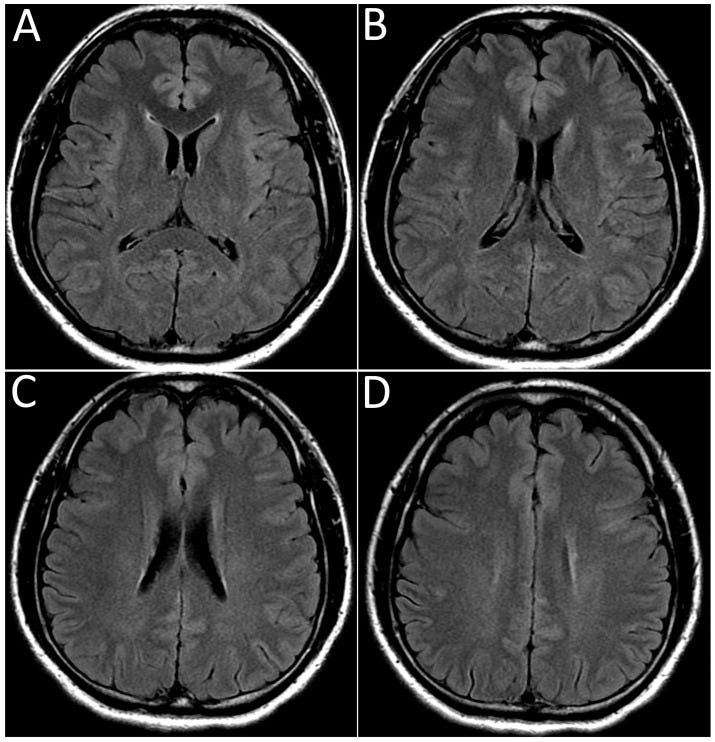

Results: All patients had typical features of ATM with acute onset of paralysis, sensory level and sphincter deficits due to spinal cord lesions demonstrated by imaging. There were 23 males (53%) and 20 females (47%) ranging from ages 21- to 73- years-old (mean age, 49 years), with two peaks at 29 and 58 years, excluding 3 pediatric cases. The main clinical manifestations were quadriplegia (58%) and paraplegia (42%). MRI reports were available in 40 patients; localized ATM lesions affected ≤3 cord segments (12 cases, 30%) at cervical (5 cases) and thoracic cord levels (7 cases); 28 cases (70%) had longitudinally-extensive ATM (LEATM) involving ≥4 spinal cord segments (cervicothoracic in 18 cases and thoracolumbar-sacral in 10 patients). Acute disseminated encephalomyelitis (ADEM) occurred in 8 patients, mainly women (67%) ranging from 27- to 64-years-old. Three ATM patients also had blindness from myeloneuritis optica (MNO) and two more also had acute motor axonal neuropathy (AMAN).